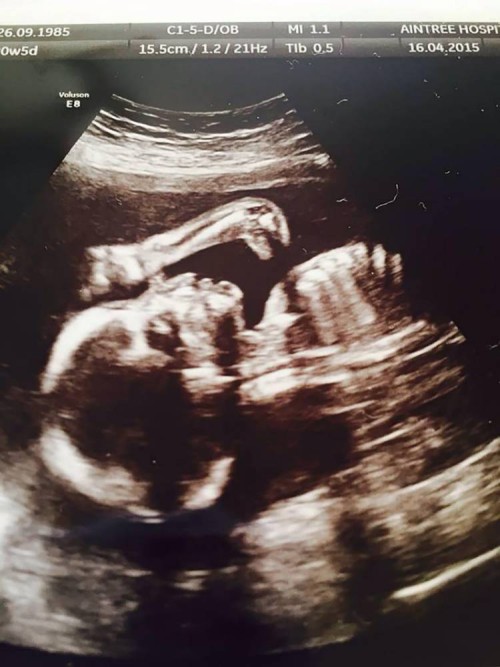

गर्भवती महिलाको ‘अल्ट्रासाउन्ड’ मा देखियो डाइनासोर

\"ultrasoundलिभरपुल । पाँच हप्तापछि छोरीकी आमा बन्न लागेकी लिभरप्ुलकी लियेन सिलेभन आफ्नो बच्चाको स्थितीबारे बुझ्न अस्पताल गइन् । त्यहाँका डाक्रहरुले उनको अल्ट्रासाउन्ड गरे । अल्ट्रासाउन्डमा बच्चाको जुन रुप देखियो त्यो देखेर लियोन चकित भइन्। अंग्रेजी वेबसाइट मिरर डट कमका अनुसार लियेन जब आफ्नो अल्ट्रासाउन्ड परिक्षण पछि फर्किइन् तब उनले आफ्नो रिपोर्टमाथि त्यति धेरै ध्यान दिइनन् । तर पछि लियेनकी साथी जेनीले अल्ट्रासाउन्डको स्क्यान रिपोर्टमा देखिएको आकृतिको बारेमा लियेनलाई जानकारी गराइन् । ‘मलाई यस बारेमा केही पनि थाहा थिएन, जेनीले पछि मलाई यसबारे जानकारी दिइन्, ’ २९ वर्षीया लियोनले भनिन् । ‘तर, एकचोटी हेरिसकेपछि तपाईंलाई साँच्चिकै रिपोर्टमा डाइनासोरको आकृती पाउनुहुन्छ ।’ यो कसरी भयो यसका बारे अहिले नै केही पत्ता लाग्न सकेको छैन । यद्यपी, उनकी छोरी भने स्वस्थ रहेको डाक्टरले जानकारी दिएका छन् ।